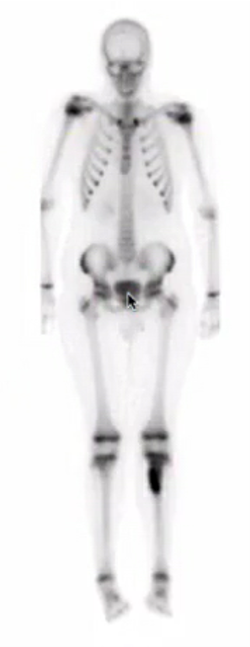

painful scoliosis

osteoid osteoma in the posterior elements